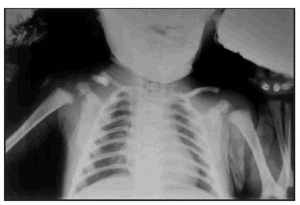

Pruebas complementarias: hemograma, hemocultivos, frotis periféricos, eco renal y radiografía de tórax, normales; urocultivo positivo para Escherichia coli (> 100.000 colonias); radiografía de clavículas: falta de unión y acabalgamiento del tercio medio de la clavícula derecha con el tercio externo.

A los 5 meses de vida es visitado en la consulta de pediatría de nuestro hospital, donde se aprecia una deformidad evidente en región medioexterna de la clavícula derecha, con claro desplazamiento a la palpación de los extremos óseos, que evidencia su falta de unión, por lo que se practica nueva radiografía de clavícula que confirma el diagnóstico (fig. 1).

Figura 1. Radiografía de clavículas en la cual se aprecia la falta de unión y acabalgamiento del tercio medio de la clavícula derecha con el tercio externo.